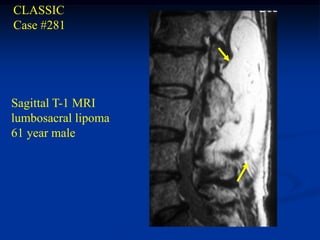

CLASSIC

Case #281

Sagittal T-1 MRI

lumbosacral lipoma

61 year male

Lumbosacral Lipoma The lumbosacral lipoma variant is frequently associated with a spinabifida defect in the spine and can be seen in both the pediatric and adult age group. These lesions can be associated with both intra- dural and extradural lipomas and can result in neurological deficiency. The MRI image will show the characteristic high signal response on the T-1 weighed image, like all other forms of lipomas. Treatment consists of a marginal surgical resection, including the lesions within the vertebral canal. A low recurrence rate is anticipated.

CLASSIC Case #281 Sagittal T-1MRI lumbosacral lipoma 61 year male